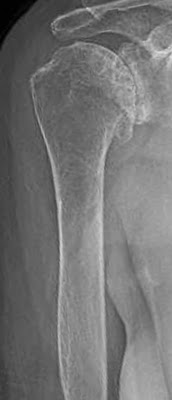

The first key view is the anteroposterior in the plane of the scapula taken so that the x-ray beam passes through the glenohumeral joint. This view shows the superior-inferior position of the humeral head relative to the glenoid, the presence of osteophytes on the humeral head and glenoid, joint space narrowing, the degree of medial displacement of the humerus in relation to the lateral acromial line, the quality of the humeral and glenoid bone, the presence of loose bodies, and the presence of humeral head collapse or deformity.

When taken properly, the standardized anteroposterior and axillary views indicate the thickness of the cartilage space between the humerus and the glenoid, the relative positions of the humeral head and the glenoid, the presence of osteophytes, the degree of osteopenia, and the extent of bony deformity and erosion.

Since arthritis usually involves the central aspect of the humeral head,

joint space narrowing is most evident on the truth view as opposed to images made with the arm at the side. Of even greater importance is the ability of the axillary ‘truth’ view to show posterior subluxation or ‘functional decentering’ that is not evident in images taken with the arm at the side.

A third view, the templating view, is obtained when humeral arthroplasty is being considered. This view is an anteroposterior (AP) view of the humerus taken with the arm in 30 degrees of external rotation relative to the x-ray beam with a magnification marker added. This view places the humeral neck in maximal profile and allows a comparison of proximal humeral anatomy with that of various humeral prostheses. In templating, it is important to recognize that the humeral canal is not cylindrical – the medial-lateral dimension is usually wider than the anteroposterior dimension so that the AP view may overestimate the size of the stem that will fit the diaphysis. This view is also useful for determining whether sufficient osteoporosis is present to merit special consideration at the time of arthroplasty